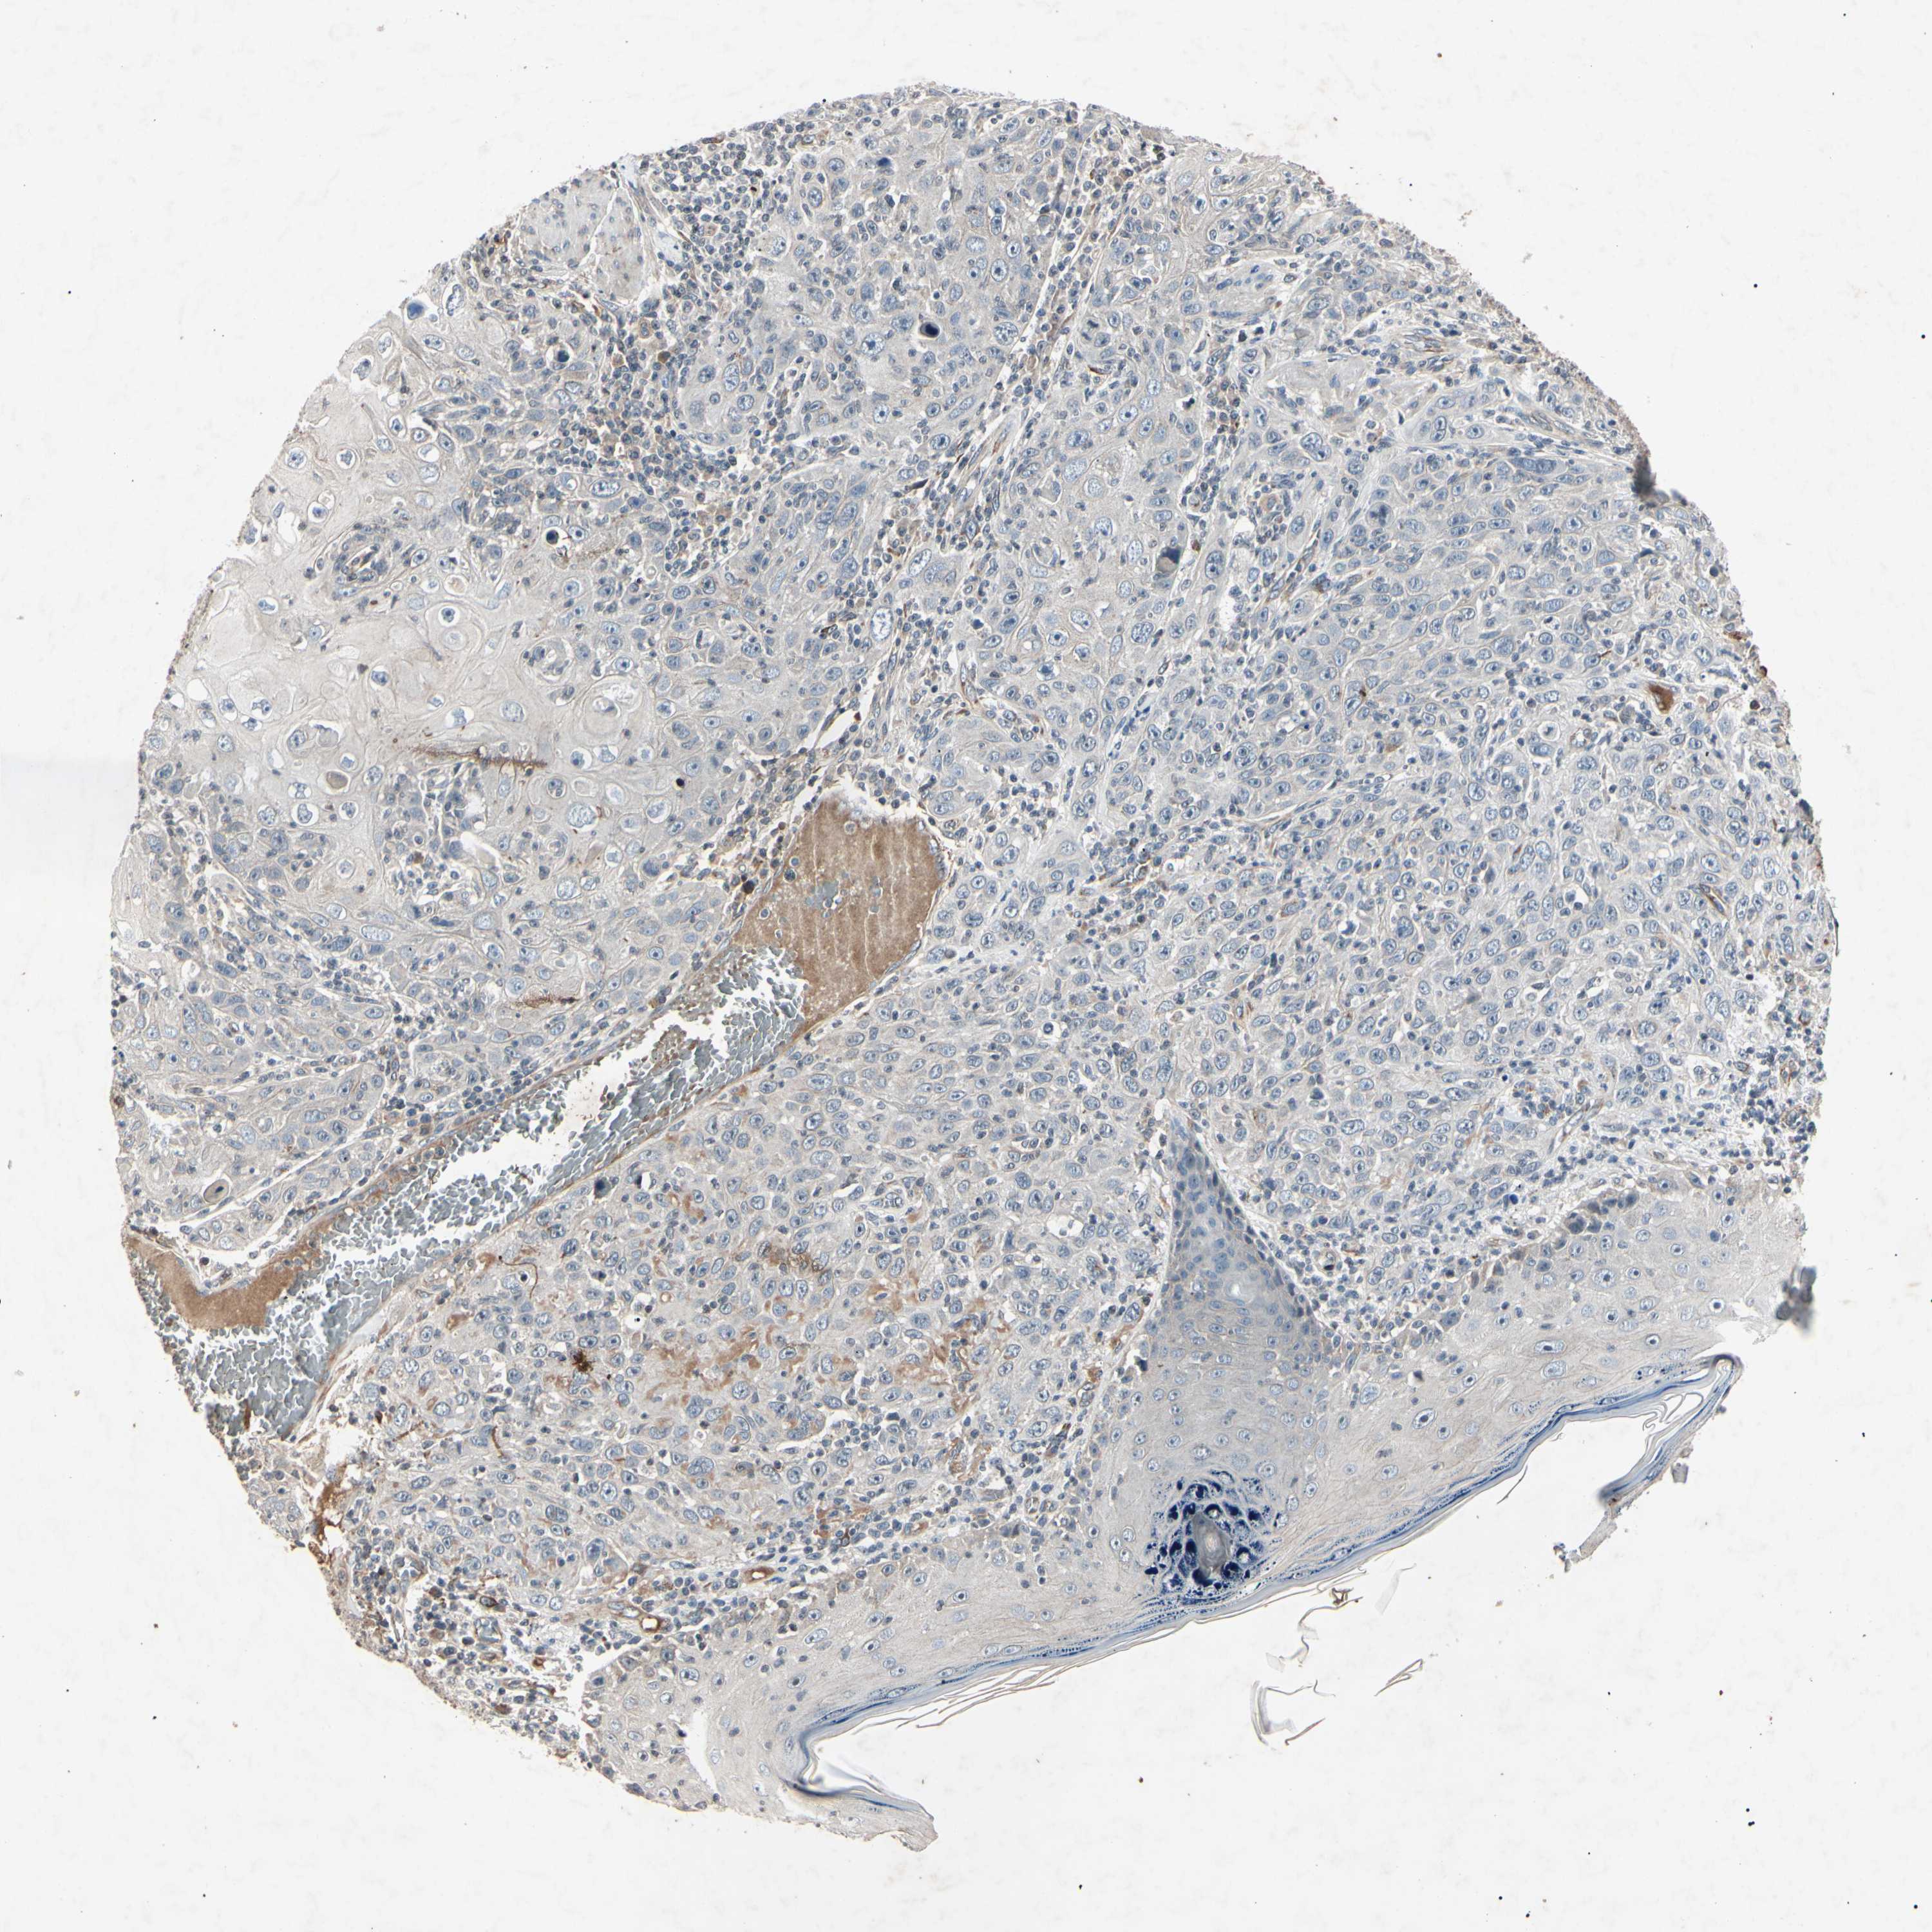

CANCER SKIN CANCER Show tissue menu

Basal cell and squamous cell cancer

SKIN CANCER - Protein expressioni

A mouse-over function shows sample information and annotation data. Click on an image to view it in a full screen mode. Samples can be filtered based on level of antibody staining by selecting one or several of the following categories: high, medium, low and not detected. The assay and annotation is described here.

Each image is clickable and will lead to virtual microscopy that enables deeper exploration of all samples and also displays staining intensity scores, fraction scores and subcellular localization as well as patient and tissue information for each sample.

Antibody CAB009966

Squamous cell carcinoma, NOS